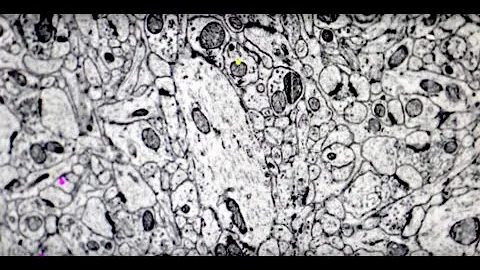

The Connectome: The Herculean Task Of Modeling A Brain

Unravel the mysteries of the human brain with this captivating video! Discover the incredible complexity of neurons, explore the ...